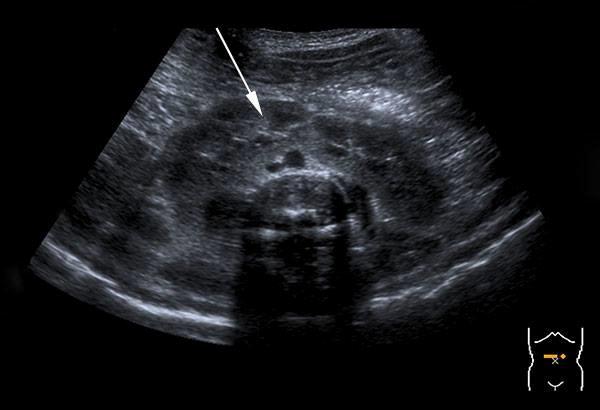

Posterior urethral valve

What is Posterior urethral valves?

most common congenital obstructive lesion of the urethra

congenital folds act of male urethra act as valves to obstruct excretion

What is the sonographic appearance of Posterior urethral valves?

marked distention bladder

hydronephrosis

hydroureter

oligohydramnios

keyhole sign

Posterior urethral valve

What is a keyhole sign?

What is the major concern for babies with posterior urethral valves?

baby can't urinate

leading to

olighydramnios

pulmonary hyperplasia

risk of bladder rupture causing urinary ascites

What is the most common cause of death for fetus with posterior urethral valves?

pulmonary hyperplasia